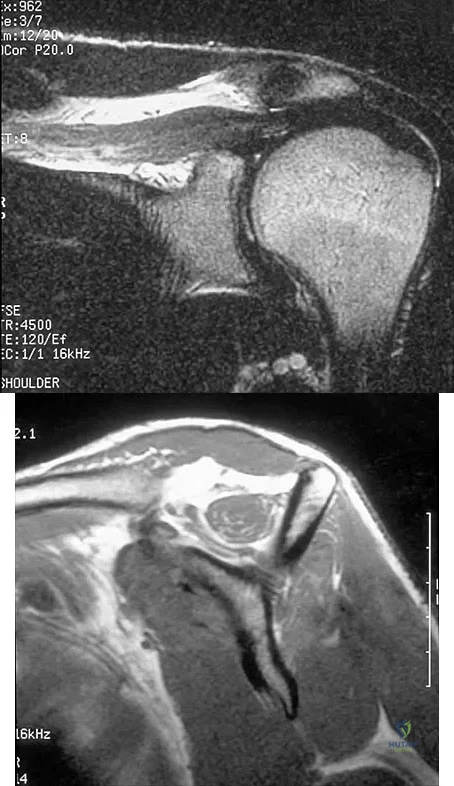

In patients older than age 40 years who sustain a first-time anterior dislocation of the shoulder, prolonged morbidity is most commonly associated with

In the study done by Pevny and associates, 35% of patients older than age 40 years sustained rotator cuff tears and 8% had axillary nerve palsies. All of the patients with axillary nerve palsy also had rotator cuff tears. Imaging of the rotator cuff is indicated in this age group. The incidence of recurrent instability in patients older than age 40 years is 10% to 15%. Pevny T, Hunter RE, Freeman JR: Primary traumatic anterior shoulder dislocation in patients 40 years of age and older. Arthroscopy 1998;14:289-294. Sonnabend DH: Treatment of primary anterior shoulder dislocation in patients older than 40 years of age: Conservative versus operative. Clin Orthop 1994;304:74-77.

Question 20High Yield

Explanation

Functional improvement after revision rotator cuff surgery is most likely to occur in patients with an intact deltoid, good-quality rotator cuff tissue, preoperative active elevation alone to 90 degrees, and only one prior rotator cuff repair. In this patient, the compromised deltoid origin might make functional improvement less likely. Djurasovic M, Marra G, Arroyo JS, et al: Revision rotator cuff repair: Factors influencing results. J Bone Joint Surg Am 2001;83:1849-1855. Bigliani LU, Cordasco FA, McIlveen SJ, et al: Operative treatment of failed repairs of the rotator cuff. J Bone Joint Surg Am 1992;74:1505-1515.